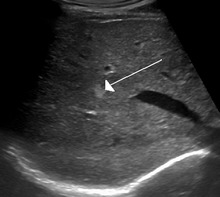

Hemangioma of the liver as seen on ultrasound

A cavernous liver hemangioma or hepatic hemangioma is a benign tumour of the liver composed of hepatic endothelial cells. It is the most common liver tumour, and is usually asymptomatic and diagnosed incidentally on radiological imaging. Liver hemangiomas are thought to be congenital in origin.[7] Several subtypes exist, including the giant hepatic hemangioma, which can cause significant complications.